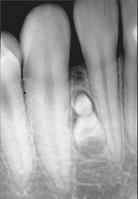

组图为牙瘤的外观及X 线表现,有关此病的描述错误的是 ( )

- A.绝大多数为恶性

- B.生长缓慢,早期无自觉症状

- C.由牙胚组织异常发育增生而形成

- D.X 线可见类似发育不全牙的影像

- E.多见青年人

正确答案及解析

A